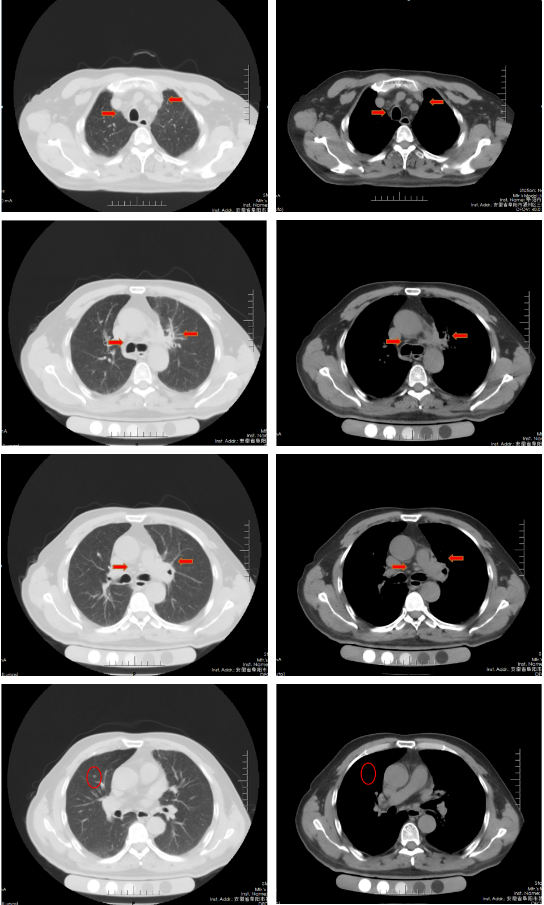

胸部增强CT(2022-02-12):左肺门及纵隔内见团块状软组织密度影,大小约62mm×42mm,边界不规整,内见血管影穿行,增强扫描呈轻度强化,局部支气管狭窄,远端肺内见片状磨玻璃密度影,边界欠清。右肺上叶见结节状密度增高影,较大直径约为8mm,增强扫描呈轻中度强化,右侧斜裂见长径约为6mm的高密度影,增强扫描未见明显强化;两肺透亮度增强,左肺下叶胸膜下囊状透光区。余气管、支气管通畅,未见明显狭窄、阻塞。纵隔和左肺门区见多发肿大淋巴结影,部分融合。两侧胸腔无明显积液。胸部CT诊断:左肺门及纵隔内占位,考虑肺Ca;纵隔及左肺门淋巴结肿大;右肺上叶结节,转移可能;右侧斜裂下结节;两肺肺气肿、左肺下叶肺大泡。

胸部CT(2022-04-12):左肺门及纵隔内见团块状软组织密度影,大小约57mm×37mm,边界不规整,局部支气管狭窄,远端肺内见片状磨玻璃密度影,边界欠清。右肺上叶见结节状密度增高影,较大直径约为9mm,右侧斜裂见长径约为7mm的高密度影;两肺透亮度增强,左肺下叶胸膜下囊状透光区;两肺可见索条状影。余气管、支气管通畅,未见明显狭窄、阻塞。纵隔和左肺门区见多发肿大淋巴结影,部分融合。两侧胸腔无明显积液。胸部CT诊断:左肺占位复查;纵隔及左肺门淋巴结肿大;右肺上叶结节,转移可能;右侧斜裂下结节;两肺肺气肿、左肺下叶肺大泡。

治疗后评价:经过EP方案治疗后两周期,患者仍有咳嗽、咳痰及左侧胸痛,症状无缓解,且出现体重下降;影像学检查提示左肺病灶及纵膈淋巴结及肺门淋巴结较前缩小不明显(缩小<30%),疗效评价SD。总体效果欠佳。

胸部CT(2022-07-15):双侧肺野透亮度增加,以两上肺和胸膜下明显。双肺纹理增多、增粗,紊乱,左肺上叶条片状高密度灶,大小约45mm×19mm,小叶间隔增厚。气管、左右主支气管无明显狭窄。纵隔内未见肿大淋巴结影。两侧胸腔无明显积液。胸部CT诊断:左上肺门占位复查;慢性支气管炎-肺气肿样改变。

治疗后评价:患者经过EP方案联合斯鲁利单抗治疗四周期后,患者咳嗽、咳痰及左侧胸痛症状消失,体重逐渐恢复;影像学提示左肺病灶及纵膈淋巴结及肺门淋巴结较前明显缩小(缩小>30%),右肺结节基本消失;疗效评价:PR(接近CR)。

胸部CT(2022-08-30):双侧肺野透亮度增加,以两上肺和胸膜下明显。双肺纹理增多、增粗,紊乱,左肺上叶见条片状高密度灶,大小29mm×18mm,小叶间隔增厚,两肺下叶见囊状透亮区。气管、左右主支气管无明显狭窄。纵隔内未见肿大淋巴结影。两侧胸腔无明显积液。胸部CT诊断:左上肺门占位复查;慢性支气管炎-肺气肿样改变;两肺下叶肺气肿。

治疗后评价:患者经过斯鲁利单抗单药维持治疗两周期后,患者未再出现咳嗽等症状,体重逐渐增加。影像学提示左肺病灶及纵隔淋巴结及肺门淋巴结、右肺结节基本消失,疗效评价接近CR。

病例小结

该患者为ⅣB期小细胞肺癌,一线采用标准化疗方案(EP)治疗2周期后疗效评估:SD,患者化疗敏感性不高;第二阶段治疗根据2022年CSCO小细胞肺癌诊疗指南,患者采用斯鲁利单抗联合EP方案,治疗2周期后体力状况明显改善,4周期后疗效评估:PR;第三阶段采用斯鲁利单抗单药维持治疗,2周期后影像学评估,左肺病灶及纵膈淋巴结及肺门淋巴结、右肺结节基本消失,疗效评估:接近CR。